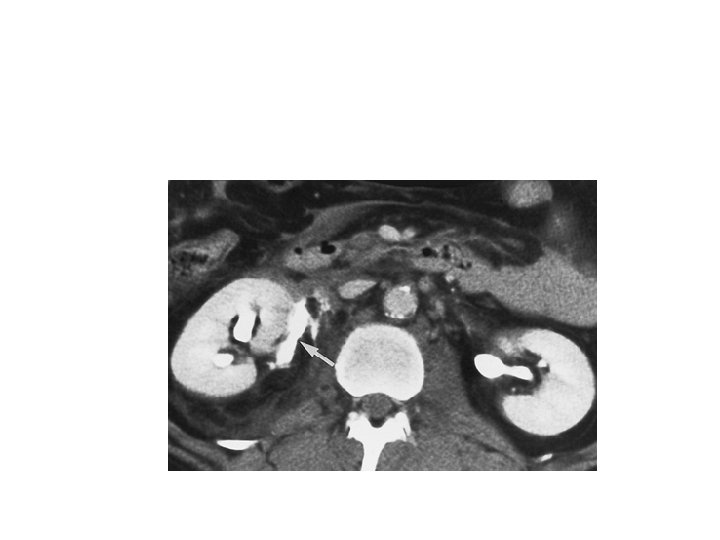

Whom to work up • Penetrating trauma: EVERYONE • Pediatric patients with microscopic hematuria. • Blunt trauma: Image with CT if: • gross hematuria • microhematuria plus shock • microhematuria plus acceleration/deceleration Mee et al. (1989) Hardeman et al (1987

Imaging of trauma patient with hematuria • CT preferred – With contrast – With “delayed” films (mandatory) – Why not get CT cystogram too? • Standard intravenous pyelogram (IVP): Forget it • “One Shot” intraoperative IVP – 2 cc/kg intravenous contrast – Single film at 10 minutes

AAST Organ Injury Severity Scale for the Kidney